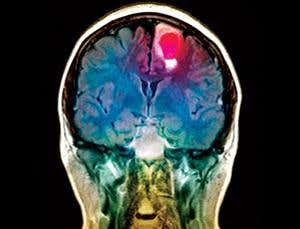

Target acquired (Image: Simon Fraiser/SPL)

GENETICALLY modified stem cells are to be injected into the brains of cancer patients, where they will convert an inactive cancer drug into a potent and targeted tumour-killing agent.